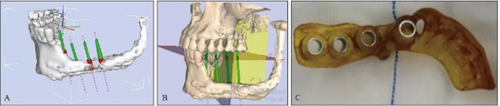

2016年4月27日根據(jù)患者條件設(shè)計并3D打印數(shù)字化種植導(dǎo)板(圖4)

并于左側(cè)腓骨移植區(qū)植入4顆Nobel Active 4.3 mm×11.5 mm種植體+RP 4.5 mm復(fù)合基臺(型號36626)(圖5)。